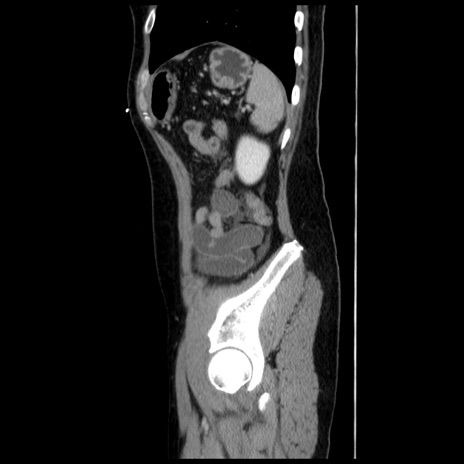

横断像

【症例】 50歳代女性

【主訴】 腹痛

【現病歴】前日生レバーを食べた。今朝に排便あり。 昼前に突然発症の腹痛を生じ、当院救急外来を受診した。

【既往歴】 子宮筋腫にてで子宮全摘後

【身体所見】 意識清明、腹部:平坦、軟、下腹部やや左を中心に圧痛・反跳痛あり、筋性防御あり

【データ】WBC 7800、CRP 0.07